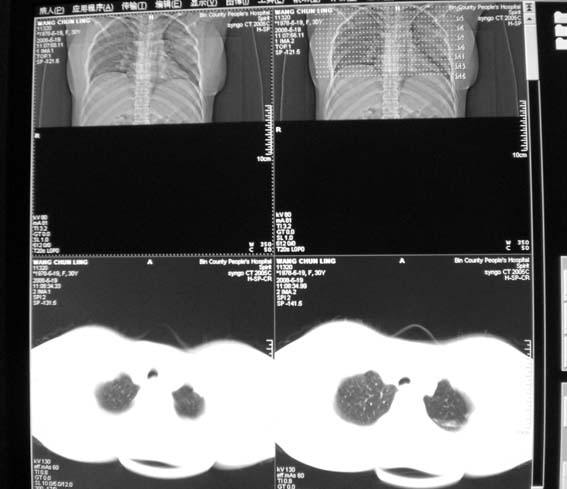

标题: CT13529:肺结核?请会诊!

女,30岁,怀孕后3个月,拍片时肺结核,抗结核治疗4个月复查。

请把原来的平片发来看看。

以下是引用形影不离在2008-5-19 20:27:00的发言:[br]请把原来的平片发来看看。

有疗效吗?

既然抗结核治疗4个月,一定做了结核相关检查,建议与原片比较看治疗效果,也可结合纤支镜取病理检查。